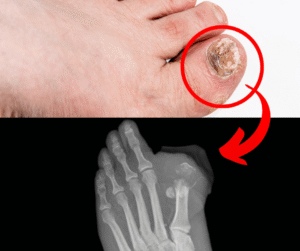

Ich möchte Ihnen einige Informationen geben. Zunächst einmal: Nagelpilz ist zwar nicht immer lästig oder schmerzhaft, aber das heißt nicht, dass Sie die Behandlung aufschieben sollten. Wenn Sie gelbe Nägel oder andere Anzeichen von Pilzbefall bemerken, behandeln Sie diese sofort, denn der Pilz wird täglich stärker und schwieriger zu bekämpfen.

Unbehandelt kann es, wie Sie in den folgenden Bildern sehen, sogar zu einer Amputation kommen.